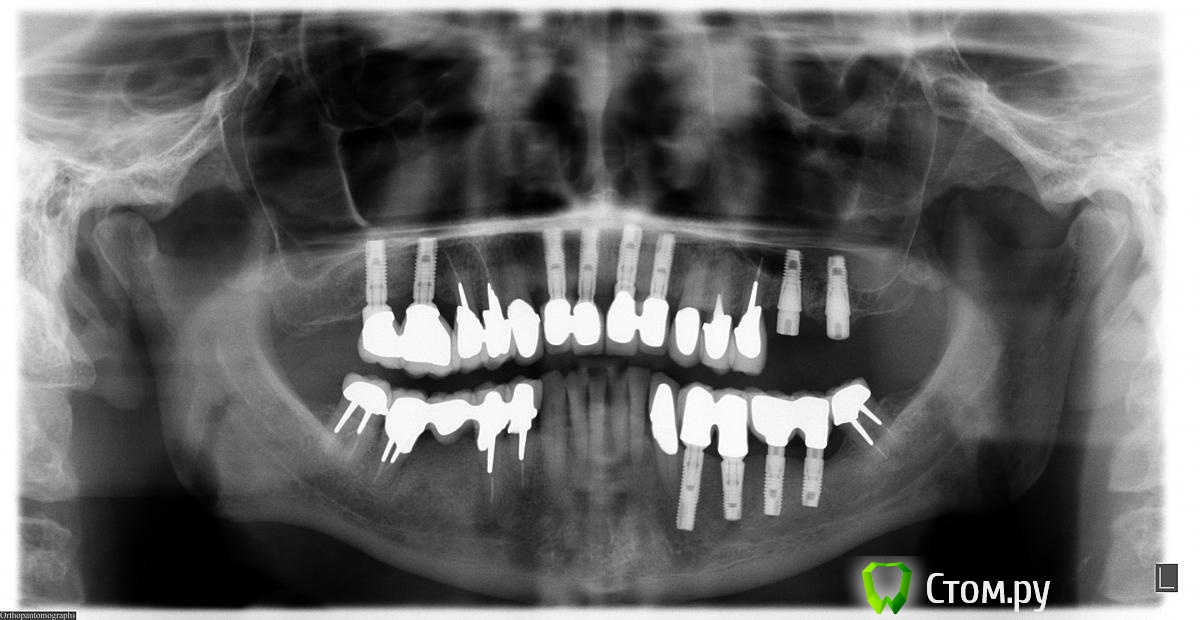

Doc Опубликовано 5 мая, 2014 Поделиться Опубликовано 5 мая, 2014 2004 год, первое посещение. 2004 год, первые имплантаты 2009 год, добавили два имплантата в область 26-27, которые по просьбе пациента были оставлены "без гарантии, пока сами не запросятся наружу", что и случилось через пять лет. Пациент претензий не имел. Сегодня утром, 5 мая 2014 года: По мне так для пациента возраста 68 лет через десять лет упорного жевания картина из серии "дай Бог каждому!". 8 Ссылка на комментарий